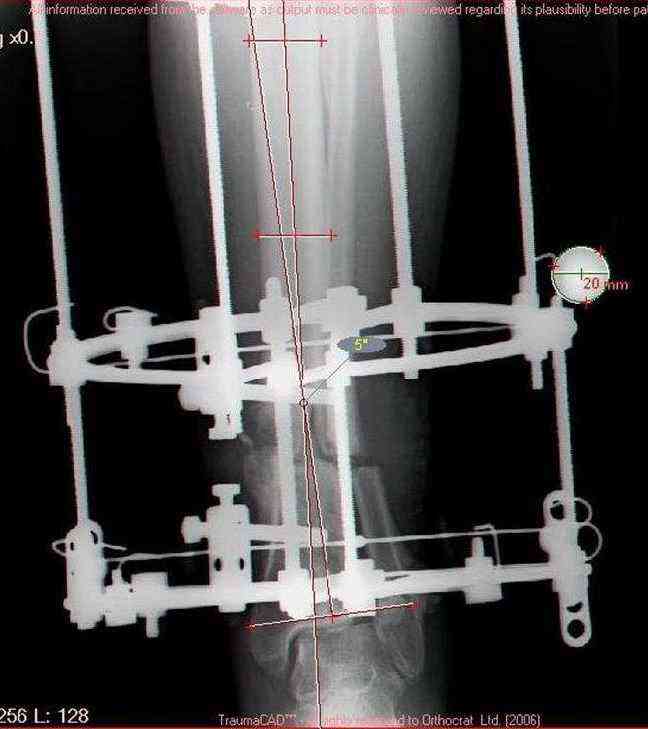

Male 54 years old, diabetic, blind in both eyes, with infected (MRSA) non union distal tibia after fracture 8 month ago. In acute phase treated by ORIF with LCP tibia and fibula. Treatment complicated by infection and after 6 month hardware was removed and treatment continued by cast fixation. You can see malposition of fragments In this stage beginning treated by Ilizarov fixation with use Hexapod system, allows anatomical position of fragments and you see signs of union.

Sorry, I wiil tray now pictures of my case.